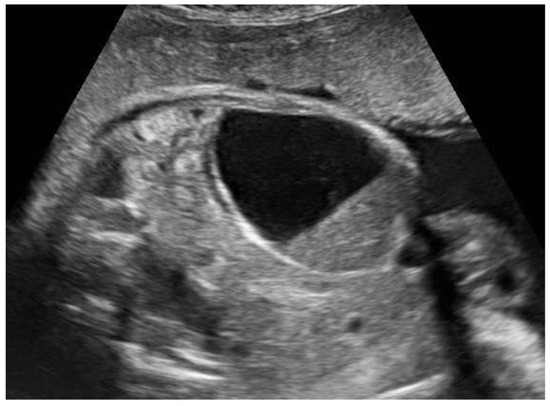

Figure 5. Fetal ovarian cyst at 35 weeks of gestation described as mixed in its content (42 × 33 × 29 mm). The central rounded formation, presumably a blood clot, was not vascularized at Power Doppler, and at postnatal follow-up evaluations, the cyst progressively decreased until disappearing within a month.